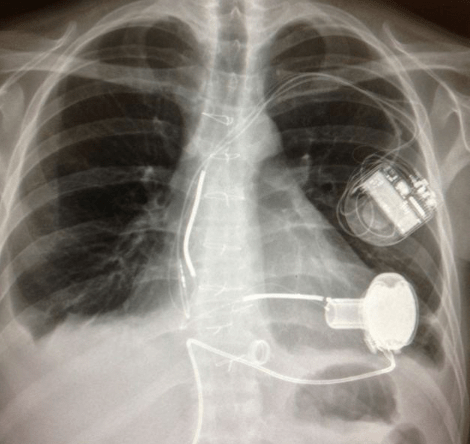

Οταν ανάρρωσε επέστρεψε στην Βρετανία, θεωρώντας ότι η «Οδύσσειά» του είχε τελειώσει, ωστόσο, μετά από μερικές εβδομάδες κατέρρευσε μέσα σε ένα σουπερ μάρκετ και υποβλήθηκε εσπευσμένα σε εγχείρηση ανοιχτής καρδίας για να τοποθετηθεί ειδικό μηχάνημα στις βαλβίδες της καρδιάς.

Πλέον, ο Αντριου, που συνεχίζει να νοσηλεύεται στο νοσοκομείο περιμένει υπομονετικά για να κάνει μεταμόσχευση καρδιάς, ενώ ο ίδιος δηλώνει αρκετά τυχερός και πιστεύει ότι έχει ακόμη μια μάχη να κερδίσει.